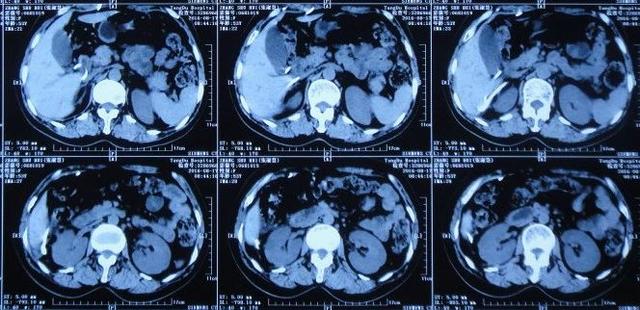

出院后1年零4个月即2015年12月8日(脑室腹腔分流术后1年零5个月),又因“肠梗阻(不全性)”,第2次住入之前手术的医院,当天查腹部CT:仍然有积液(图-6)。给予静脉抗感染、灌肠通便等对症支持,治疗2周后,肠梗阻症状改善后出院。

图-6:2015年12月8日腹部CT

住院次日即2016年8月17日,查腹部CT:仍有腹腔积液(图-8)。

图-8:2016年8月17日腹部CT